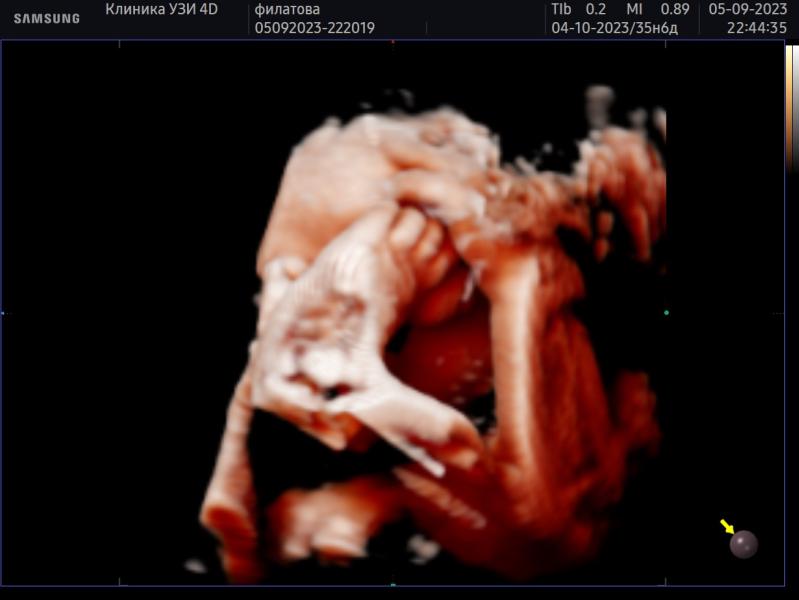

Фотосессия мини малыша: как прошла, параметры, сложности? Делимся опытом и переживаниями

Наша последняя фотосессия 🙏малыш миниатюрный будет как и дочь надеялась что будет чуть крупнее но нет, опять прогноз на 2800/2900🙏еле заставили руки и ноги с лица убрать😁